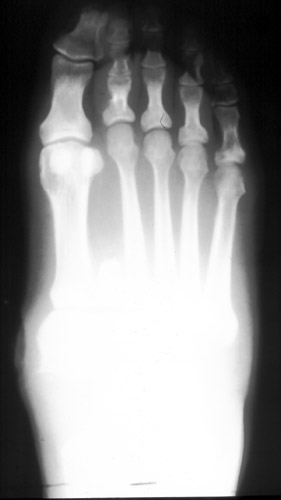

Advanced Imaging of the Diabetic Foot and Its Complications

Imaging of the Diabetic Foot and Its Complications